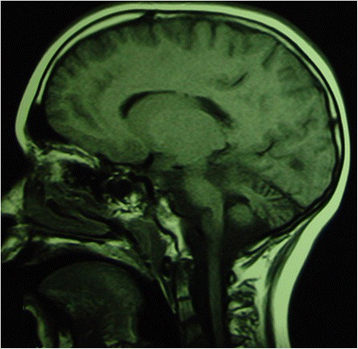

Background: Ataxia is a sign of different disorders involving any level of the nervous system and consisting of impaired coordination of movement and balance. It is mainly caused by dysfunction of the complex circuitry connecting the basal ganglia, cerebellum and cerebral cortex. A careful history, physical examination and some characteristic maneuvers are useful for the diagnosis of ataxia. Some of the causes of ataxia point toward a benign course, but some cases of ataxia can be severe and particularly frightening.

Methods: Here, we describe the primary clinical ways of detecting ataxia, a sign not easily recognizable in children. We also report on the main disorders that cause ataxia in children.

Results: The causal events are distinguished and reported according to the course of the disorder: acute, intermittent, chronic-non-progressive and chronic-progressive.